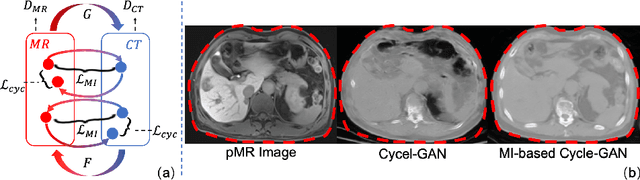

Abstract:Thermal ablation is a minimally invasive procedure for treat-ing small or unresectable tumors. Although CT is widely used for guiding ablation procedures, the contrast of tumors against surrounding normal tissues in CT images is often poor, aggravating the difficulty in accurate thermal ablation. In this paper, we propose a fast MR-CT image registration method to overlay a pre-procedural MR (pMR) image onto an intra-procedural CT (iCT) image for guiding the thermal ablation of liver tumors. By first using a Cycle-GAN model with mutual information constraint to generate synthesized CT (sCT) image from the cor-responding pMR, pre-procedural MR-CT image registration is carried out through traditional mono-modality CT-CT image registration. At the intra-procedural stage, a partial-convolution-based network is first used to inpaint the probe and its artifacts in the iCT image. Then, an unsupervised registration network is used to efficiently align the pre-procedural CT (pCT) with the inpainted iCT (inpCT) image. The final transformation from pMR to iCT is obtained by combining the two estimated transformations,i.e., (1) from the pMR image space to the pCT image space (through sCT) and (2) from the pCT image space to the iCT image space (through inpCT). Experimental results confirm that the proposed method achieves high registration accuracy with a very fast computational speed.